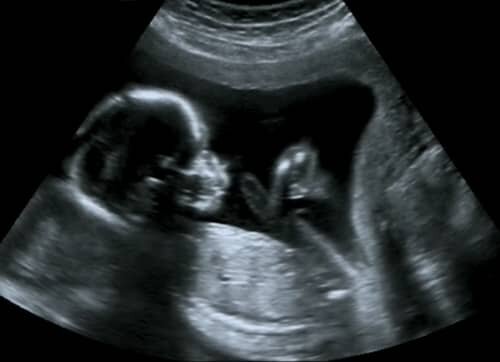

• 2nd Trimester

2nd Trimester

Months 4 through 6. The size of the fetus at the start of this trimester is about 5 inches in length and roughly 4 ounces in weight. This trimester is where the features of the fetus start to resemble that of a human being. By month 5 the fetus' limbs, muscles, and nerves are stronger and more developed which is why the mother can feel the turns, stretches, and kicks during what is known as the quickening. By the end of the 2nd trimester the fetus weighs about 1 1/2 - 2 lbs and 9 inches long